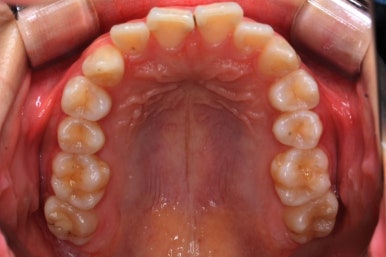

위 사진은 연산동교정치과 처음 내원하셨을 때의 입안 모습입니다. 몇 가지 모습이 관찰됩니다.

치아가 삐뚤삐뚤합니다.

위~아래 앞니가 많이 겹쳐서 아랫니가 많이 모이지 않는 "과개교합" 입니다.

앞니가 앞으로 뻐뜨러져 있습니다.

치아는 매우 가지런해졌고, 과개교합도 개선이 되었으며 뻐드러진 앞니 각도도 정상적으로 회복이 되었습니다.

치아가 가지런해졌습니다.

뻐드러진 앞니가 정상적인 각도로 회복되었습니다.

전반적인 치아들의 위치가 뒤로 이동하였습니다.